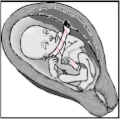

A nuchal cord is when the umbilical cord becomes wrapped around the fetus's neck.[1] Symptoms present in the baby shortly after birth from a prior nuchal cord may include duskiness of face, facial petechia, and bleeding in the whites of the eye.[1] Complications can include meconium, respiratory distress, anemia, and stillbirth.[1] Multiple wraps are associated with greater risk.[3]

| Baby in the uterus with umbilical cord wrapped around its neck and arm | |